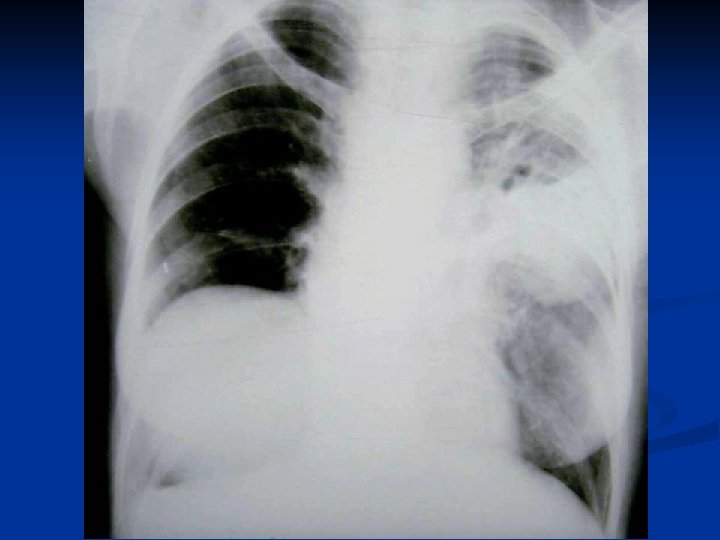

CONSIDERATII GENERALE ASUPRA CHISTULUI HIDATIC PULMONAR C. Mitrofan, A. Aldea, C. Grigorescu, I. Jitaru, C. Moldoveanu, G. Iosep, S. Bolog, M. Radulescu Clinica de Chirurgie Toracica U. M. F. Iasi

Caracteristici generale n n n Boala parazitara determinata de Taenia echinococcus granulosus. Descrisa inca de pe vremea lui Hipocrat si a lui Galen. Termenul de “chist hidatic” utilizat de Rudolphi in 1908. Localizarea pulmonara este a doua ca frecventa dupa cea hepatica. Boala cu distributie endemica in regiunea mediteraneana, Orientul Mijlociu, Australia, Noua Zeelanda, America de Sud.

Material si Metoda n Studiul de fata analizeaza retrospectiv 162 de cazuri operate in perioada 1999 – 2003.

Concluzii n n n CHP evolueaza mult timp asimptomatic sau cu simptome nespecifice. Diagnosticul precoce este deosebit de important avand in vedere evolutia acestei boli. Tratamentul medical antiparazitar (Albendazol) este indicat postoperator. Rezectia pulmonara este o metoda de rezerva in tratamentul chirurgical al CHP. Indicatia operatorie este absoluta, tehnica operatorie alegandu-se in functie de caracteristicile fiecarui caz in parte.